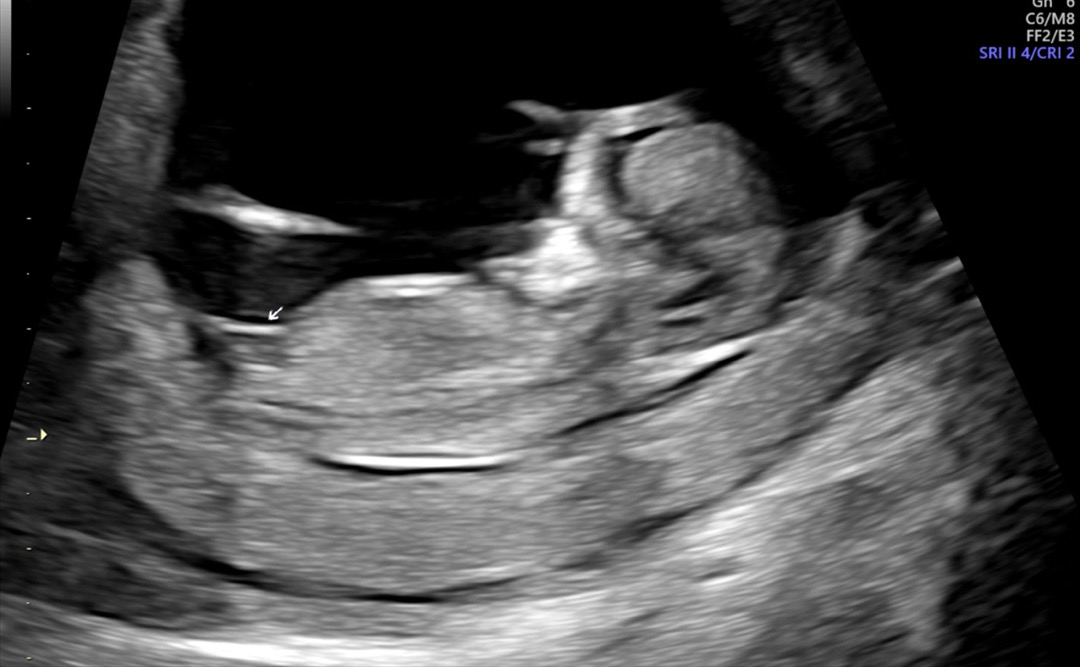

각도 잘 보시는 분들 많은 참견 부탁드려요!

많은 참여 부탁드립니다 댓글에 사진 더 올렸습니다!